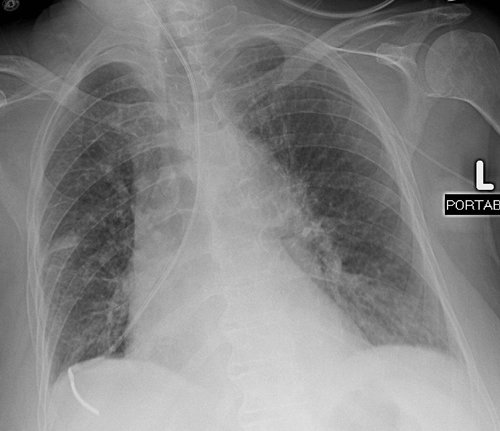

FIGURE 5-13. Hemothorax as a complication of pulmonary artery catheter placement. AP chest radiograph shows appropriate placement of a right jugular pulmonary artery catheter. However, there is complete opacification of the right hemithorax, representing acute and massive hemothorax.